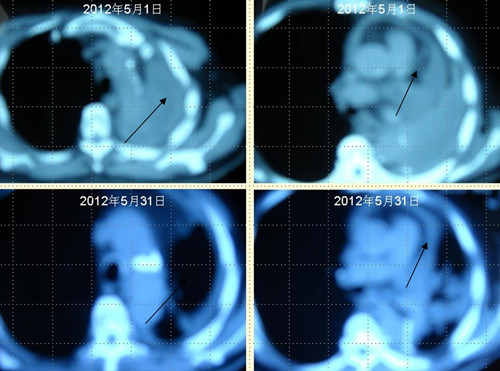

[提要] 患者王某某,男,74歲,于2009年12月在濱州醫(yī)學(xué)院附屬醫(yī)院行左肺下葉占位切除術(shù),術(shù)后病理提示為"中分化鱗狀細(xì)胞癌"侵犯支氣管壁全層,累及支氣管周圍肺組織。

肺癌王XX采用 “董氏治癌法”治療前后CT對照變化